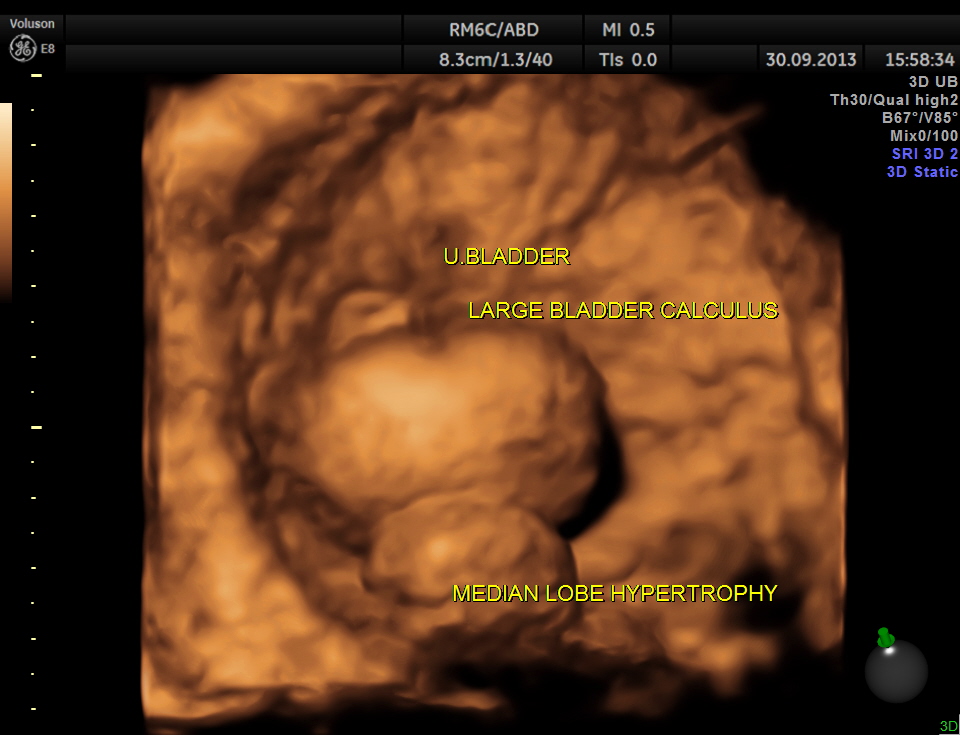

urinary bladder showed a large calculus and prominent swelling of the median lobe of the prostate.

2 D and 3 D of the bladder calculus alone.

2 D and 3 D views of the median lobe hypertrophy

The diagnosis given was Large calculus in the urinary bladder , Severe prostatic enlargement with prominent median lobe hypertrophy , causing Right sided obstructive uropathy.

The diagnosis was made with the 2D images , but the 3 D images were very helpful in explaining to the patient.